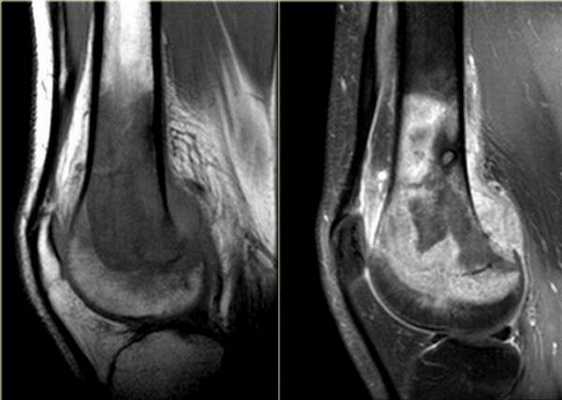

МРТ коленного сустава, разрыв передней крестообразной связки

МРТ коленного сустава. МРТ в отличии от рентгенографии представляет детальную визуализацию мягких тканей. На МР-томограмме в боковой плоскости опредляются передняя и задняя крестообразные связки (стрелки)